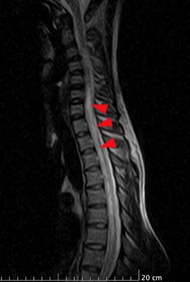

On neuroimaging, MRI cervico-thoracic spine showed T2 hyperintense lesion extending from the lower cervical to the mid-thoracic cord with minimal cord expansion, with no post-contrast enhancement, likely due to inflammatory demyelinating aetiology. (Figure 1 & 2) MRI Brain with contrast done in this patient, was reported as an essentially unremarkable study with no evidence of demyelinating plaques or any other significant abnormality (Figure 3).

Figure 1: T2 sagittal view hyperintense signal in lower cervical and midthoracic region.

Transverse myelitis is an initial presentation mainly in adults who are seropositive for MOG-AD. It is a severe, disabling condition, and with the help of antibody assessment for NMOSD and MOG, we are able to identify the causes of transverse myelitis. MOG-IgG-associated myelitis presents as acute flaccid myelitis. MOG-AD transverse myelitis is mostly longitudinally extensive (LETM). As in our case, MRI dorsolumbar spine showed a longitudinally extensive lesion extending from the lower cervical to the mid-thoracic region. It showed no post-contrast enhancement as compared to AQP4-IgG seropositive myelitis. Deep grey matter lesions are more common in MOG-IgG myelitis [7]. It can also be associated with optic neuritis and brainstem encephalitis. We can differentiate MOG-AD from NMOSD and MS, although there are few clinical and radiological similarities between MOG-AD and NMOSD but can easily differentiate from MS. Silent lesions which are commonly found in MS are absent in MOGAD [1]. MOGAD has the greatest predilection for conus medullaris resulting in sphincter involvement and bladder dysfunction [8].